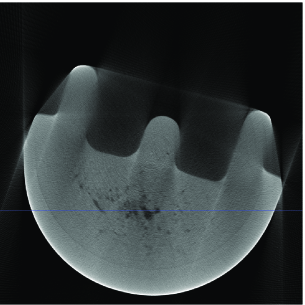

Industrial object reconstruction. We apply our proposed methods to reconstruct an industrial object from real fan-beam X-ray CT projections. First, we performed the standard fan-to-parallel beam conversion (see [7, Sec. 3.4]) and generated parallel-beam projections with spacing and measurement array size of elements, yielding frequency-domain measurements per projection. Our full mask has circular shape containing signal elements. The outer-shell mask containing pixels has been constructed from the phantom’s parallel-beam sinogram using , see Section V.

We compare the reconstruction performances of mask DORE () and DORE () with ; the mask FPC and FPC schemes using the regularization parameter ; the standard FBP method. The reconstructions of mask FPC and FPC are very similar to those of mask DORE and DORE; hence we present only the mask DORE and DORE reconstructions in this example. Figs. 3–3 show the reconstructions of the FBP, DORE, and mask DORE methods from projections whereas Figs. 3–3 show the corresponding reconstructions from limited-angle projections. Figs. 3–3 show the corresponding reconstruction profiles for slices depicted in Figs. 3–3. Observe the aliasing correction and denoising achieved by the sparse reconstruction methods.